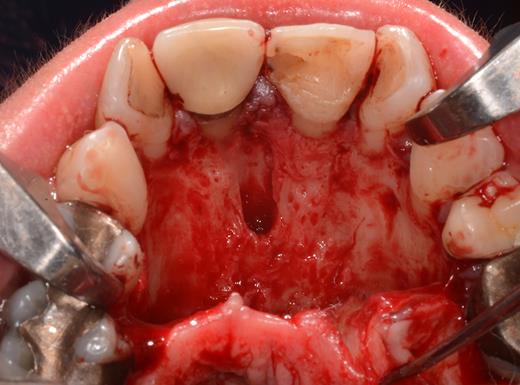

After a sulcular incision on the palatal side from teeth 15 to 25 and an incision in the midline of the palate omitting the incisive papilla and the two orifices of the NPD, two full-thickness mucoperiosteal flaps were raised. Thereafter, the incisive papilla and the whole contents of the incisive canal were enucleated (Figs 4–6). The bony incisive canal was filled with autologous bone harvested from the palatal region (bone scraper) (Fig. 7). A tension-free primary wound closure was achieved by moving the palatal flaps to the midline using single button and interdental vertical mattress sutures (Monocryl 4-0, Ethicon, Johnson & Johnson, USA) (Fig. 8). To avoid wound dehiscence and hematoma, an iodoforme gauze and a palatal plate were applied (Fig. 9). The patient was instructed to rinse three times a day with 0.1% chlorhexidine (formula hospitalis) for 2 weeks postoperatively. Sutures were removed after 14 days.

Preparation of the soft tissue of the incisive canal and the incisive papilla.